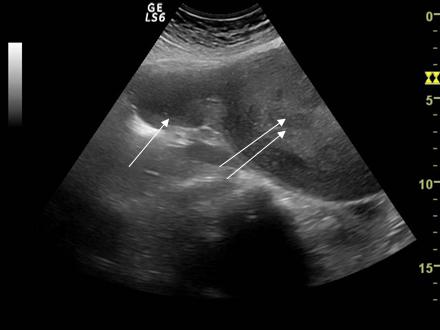

Fig. nr. 404. Colectie anecogena in lumenul trompei .Hidrosalpinx ce inconjura ovarul omonim, se remarca peretele cudat al trompei cu continut lichidian.